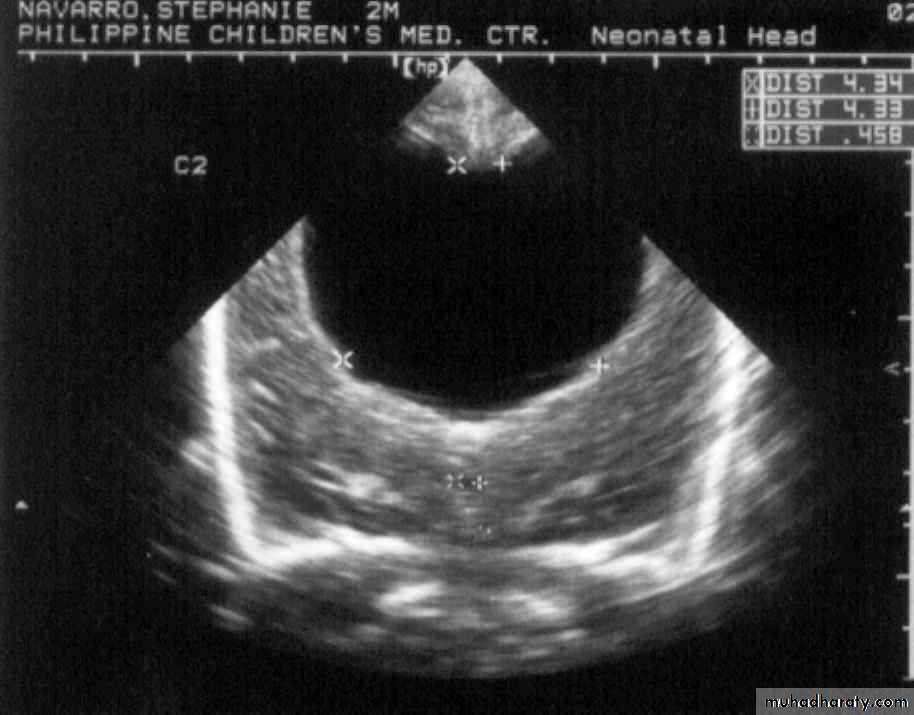

Neurulation PeriodS. N., 2 mos old, female

Marked obstructive Hydrocephalus

secondary to ARNOLD CHIARI IIMeningocoele